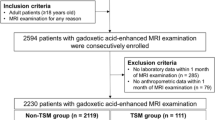

Study population

Between January and November 2016, 2128 subjects were enrolled for this study, among which 1780 patients received gadoxetate disodium and 348 other contrast agents (Fig. 1). From these, 135-s examinations in the same patient were excluded to avoid a possible bias caused by the known association between respiratory motion artifacts and prior episode of arterial phase motion. The total study population included 1993 patients (1201 men, 792 women, mean age 66.4 ± 12.8 years) consisting of 1646 (1021 men, 625 women, mean age 66.7 ± 12.5 years) scanned with gadoxetate disodium and 347 (180 men, 167 women, mean age 64.7 ± 14.0 years) with other gadolinium chelate-based extracellular contrast agents (GBCAs). Examination purpose and underlying disease included liver cirrhosis (n = 1143; 57.4%), metastasis (n = 242; 12.1%), biliary disease (n = 115; 5.8%), pancreatic disease (n = 316; 15.9%), kidney disease (n = 35; 1.8%), and other causes (n = 142; 7.1%) (Suppl. Table 1).

Additionally, a subcohort of pairs was built by matching for age, gender, and institutions. This subcohort consisted of 320 patients (149 men, 171 women, mean age 65.5 ± 12.2 years) with gadoxetate disodium and 320 patients (149 men, 171 women, mean age 65.8 ± 12.5 years) with other GBCAs. The impact of multiple arterial phase acquisition on the prevalence of substantial artifacts was assessed in patients from 3 institutions that performed both single and multiple arterial phase protocols under gadoxetate disodium administration (n = 950). Demographic characteristics were representative of the whole cohort: institution 1 (n = 140; 86 men, 54 women, mean age 65.1 ± 13.5 years), institution 2 (n = 355; 211 men, 144 women, mean age 68.2 ± 11.3 years), institution 3 (n = 455; 296 men, 159 women, mean age 68.1 ± 10.9 years).